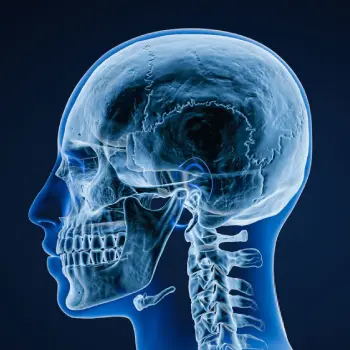

در این روش تصویر برداری یک صفحه (گیرنده یا دتکتور) در زیر عضو و قسمت مورد نظر قرار داده می شود و اشعه ایکس(دُز از اشعه جهت تشخیص) به همان قسمت که روی صفحه قرار گرفته تابنده می شود و توسط صفحه اطلاعات دریافت می شوند و همین اطلاعات پس از پردازش های لازم در نهایت عکس رادیولوژی به ما ارائه می دهد. کاربردهای رادیولوژی در منزل دقیقاً همان کاربرد رادیولوژی در بیمارستان ها می باشد از جمله بررسی انواع شکستگی ها، دررفتگی مفاصل، آرتروز مفاصل، دیدن پروتز های داخل استخوان از نظر بررسی موقعیت پروتز، آب آوردگی ریه(اِدم وافیوژن) و عفونت ریه، شکستگی دنده ها، انساد و وجود هوا در شکم و… می باشند. رادیولوژی در منزل تمام این خدمات را ارائه می دهد.

تصاویری از رادیولوژی در منزل توسط گاما پرتو